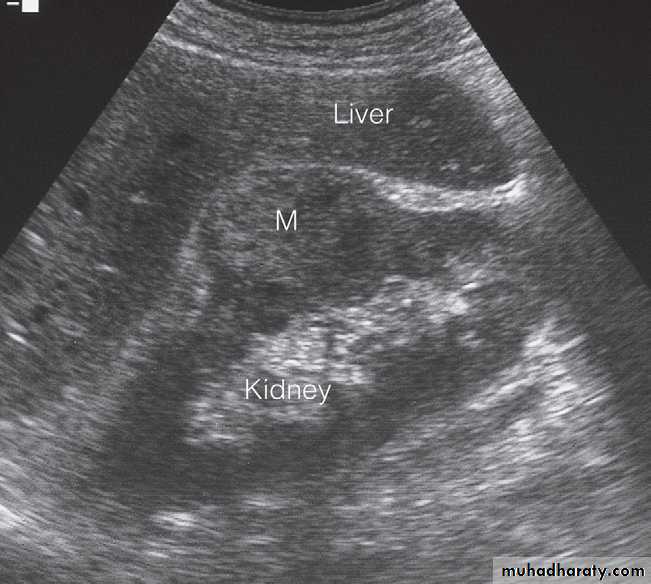

U/S :Most renal calculi of more than 5 mm in size are readily seen at ultrasound, produce intense echoes and cast acoustic shadows.

Stones in the ureters cannot be excluded on ultrasound, although stones lodged at the vesicouteric junction may be demonstrated .